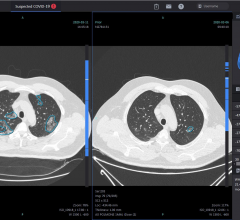

October 13, 2020 — Given recent high-profile cases of COVID-19 and to aid in the ongoing fight against the pandemic in ...